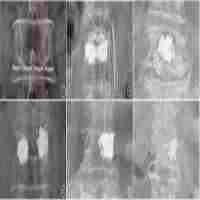

| Abstract | Background Osteoporotic vertebral fractures and their complications pose increasing risks to the elderly. The purpose of this study was to evaluate the clinical efficacy of unilateral percutaneous vertebroplasty in patients with osteoporotic vertebral compression fractures (OVCF) by assessing postoperative cement distribution. Objective This study aimed to investigate the impact of cement distribution on the efficacy of vertebral compression fracture repair to provide effective preventive and therapeutic measures, prevent postoperative vertebral re-fracture, and improve surgical outcomes. Methods A total of 170 patients who underwent unilateral percutaneous vertebroplasty at our hospital from January 2020 to December 2022 were selected. Based on the postoperative X-ray cement distribution morphology, they were divided into the good distribution group (n = 87) and the poor dispersion group (n = 83). The basic information of patients, surgery-related indicators including operation time, total hospitalization costs, postoperative hospitalization time, cement injection volume, visual analog scale (VAS) for back pain, Oswestry Disability Index (ODI) for back pain, vertebral height restoration rate, local kyphotic angle of the vertebra, and incidence of re-fracture of injured and adjacent vertebrae were compared between the two groups, and the follow-up results of all patients were recorded. Results There were no significant differences in age, gender, body mass index, fracture days, menopausal age of female patients, bone density T value, medical history, smoking history, alcohol history, and surgical segments between the two groups (P > 0.05). The VAS scores for back pain at 1 month and 1 year postoperatively were significantly lower in the good distribution group than in the poor dispersion group, with statistical significance (P < 0.05). The good distribution group had a significantly lower incidence of re-fracture of injured vertebrae and overall fracture incidence than the poor dispersion group (P < 0.05). There were no statistically significant differences in operation time, cement dosage, cement leakage, postoperative hospitalization time, adjacent vertebral fractures, postoperative vertebral height restoration rate, VAS scores for back pain at preoperative and 1 week postoperative, and ODI at preoperative, 1 week, 1 month, and 1 year postoperative between the two groups (P > 0.05). Conclusion Compared with the poor dispersion group, patients in the cement distribution group achieved better short-term clinical efficacy, and long-term prognosis effects are still under observation. Moreover, the cement good distribution group significantly reduced the incidence of re-fracture of injured vertebrae and overall fracture incidence, thereby achieving better surgical outcomes. |